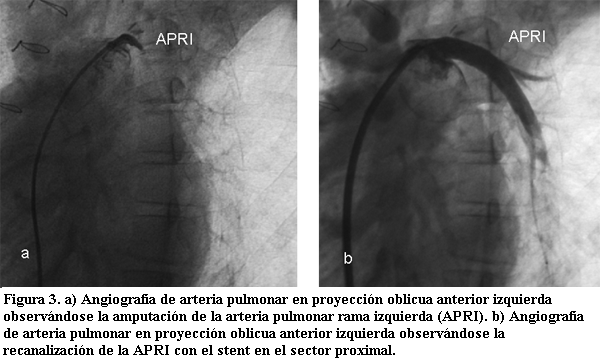

En caso de no existir pasaje a nivel del septum interauricular se puede realizar la perforación del mismo con una aguja especial (aguja de Brockenborough), o por radiofrecuencia; luego mediante un catéter “cuchilla” (catéter de Park), se hace un corte en el tabique interauricular para poder realizar la dilatación con balón; esta última es una alternativa para pacientes que requieran este procedimiento fuera del período neonatal (figuras 1 y 2).

En estas situaciones, la solución quirúrgica muchas veces se ve comprometida por tratarse de postoperatorios de cirugía cardíaca en donde el procedimiento de disección para acceder al vaso afectado suele ser muy dificultoso. Es así que el poder realizar un procedimiento de recanalización de vasos por intermedio de catéteres adquiere jerarquía. Recientemente se ha descrito una nueva técnica utilizando la radiofrecuencia en la cual con una variación de las características de las ondas de radiofrecuencia utilizada para la ablación de focos productores de arritmias, (con bajo voltaje y alta temperatura) se logra perforar estructuras y a partir de allí mediante dilataciones progresivas darle al vaso un diámetro adecuado, incluso con la utilización de stents (figura 3).